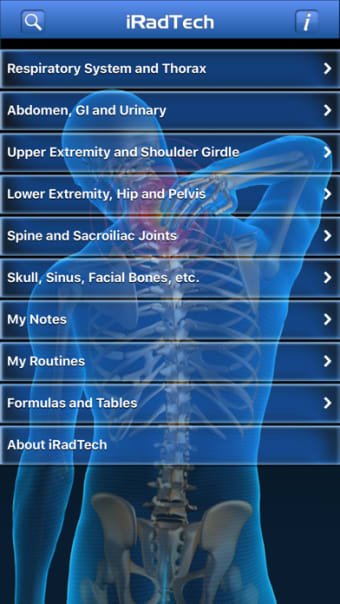

Un'applicazione versione completa per iPhone, di Ballinger e Bruckner LLP.

IRadTechè un programma completo per iPhone, che fa parte della categoria 'Medicina'.

IRadTech funziona su iOS 12.1.2 e versioni successive. La versione attuale dell'app è 4.0.1 e puoi eseguirla solo in inglese.